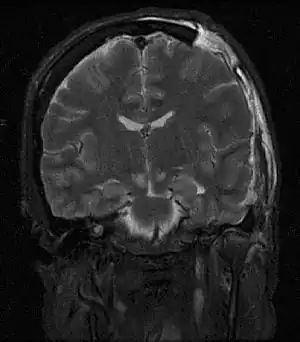

![]() | |

| MRI showing injury due to brain herniation | |